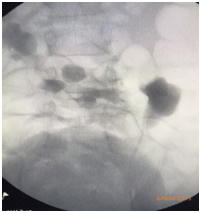

| Retrograde pyelogram | Robotic pyeloplasty | |

| Preoperative Retrograde pyelogram | Postoperative pyelogram | |